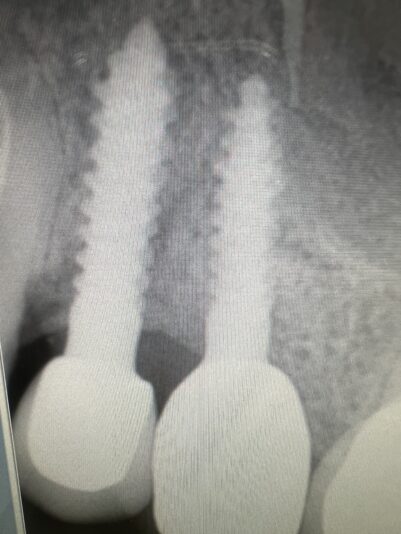

• Reply to #10 implant site

You are totally right that palatal bone is less likely to get resorption or peri-implantitis and that most problems occur on the buccal. However, as a periodontist I often get cases sent to me where they went too palatal and now there’s no palatal support for the implant. 1.5-2mm buccal and palatal is a recipe for success in my book.